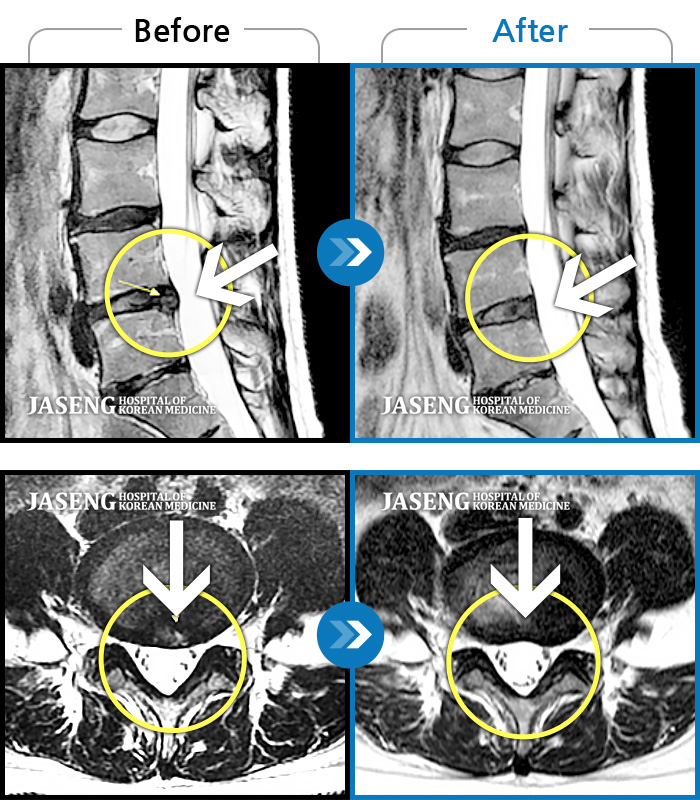

Before

After

환자에게 사전 동의를 받아 동일 조건에서 촬영되었습니다.

개인에 따라 치료 후 부작용이 발생할 수 있으니 의료진과 상담 후 치료를 진행하시기 바랍니다.

허리통증, 우측 엉덩이 통증

허리에서 다리까지 통증